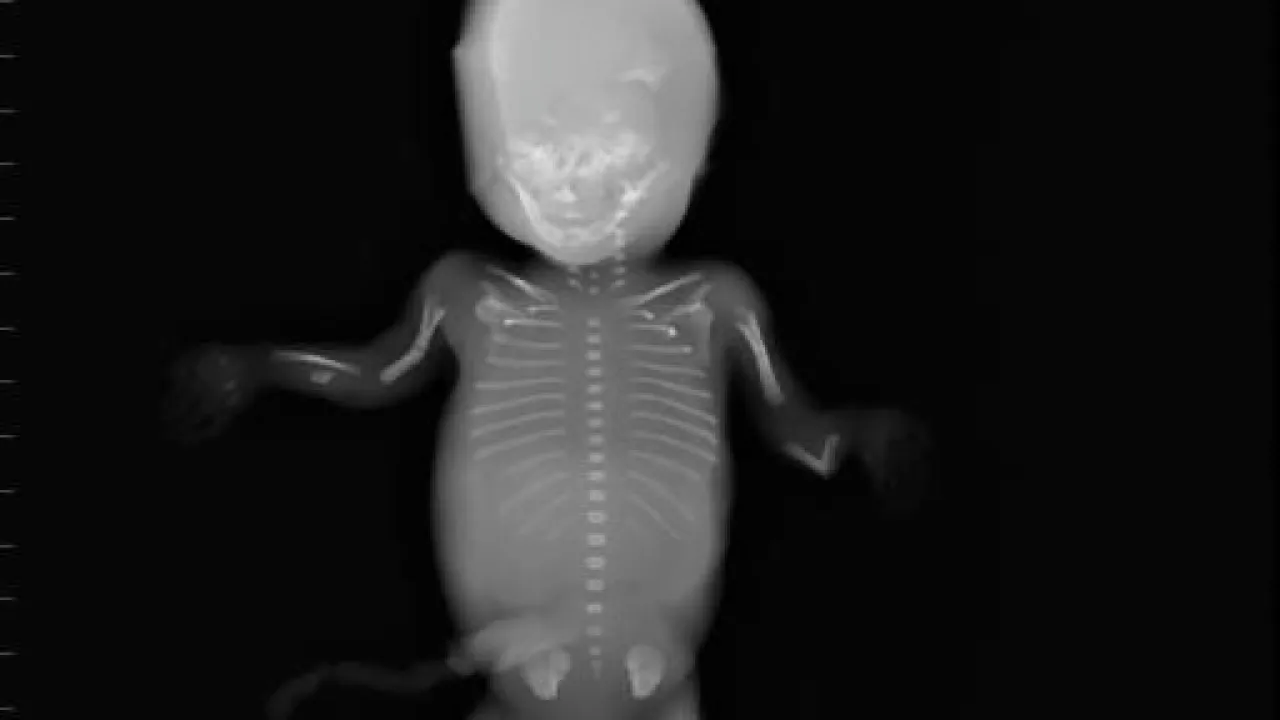

Skeleton, Twin reversed arterial profusion sequence